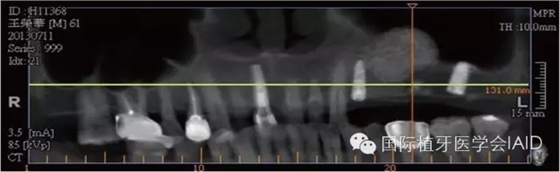

在植牙手術(shù)執(zhí)行之前,需要進(jìn)行全口檢查與軟硬組織的評估??谕馐嗄P团ccone beam CT資料搜集有助于治療計(jì)劃的擬定。在石膏模型上進(jìn)行diagnostic wax up有助于決定植體上假牙前后關(guān)系、頰舌側(cè)位置、咬合高度、及植體與植體上假牙的高度比例。使用Cone beam CT(CBCT)可以容易了解手術(shù)區(qū)硬組織條件,如Septum、骨頭高度及寬度、骨頭密度、神經(jīng)血管位置等。分析以上數(shù)據(jù)后,較容易得到可預(yù)期性的結(jié)果。

初期穩(wěn)定度在第一及第二類型的案例(>9mm; 6mm-9mm) 可以較容易達(dá)到,故通常以crestal approach進(jìn)行手術(shù)。Lateral window術(shù)式在第三型(3mm-6mm)較被建議。 若是前三個(gè)類型的初期穩(wěn)定度達(dá)到35Mpa,可以考慮當(dāng)次放置植體。若骨頭條件屬于第四型(<3mm),Lateral approach 比較建議使用,而植體可考慮等到Grafted Bone較成熟時(shí)再置入。(Fig. 1 & 2)術(shù)式的選擇與骨頭高度有密切的關(guān)系,當(dāng)骨頭垂直高度小于3 mm(于兩顆植體中),植體應(yīng)考慮 Bone graft穩(wěn)定后再植入。